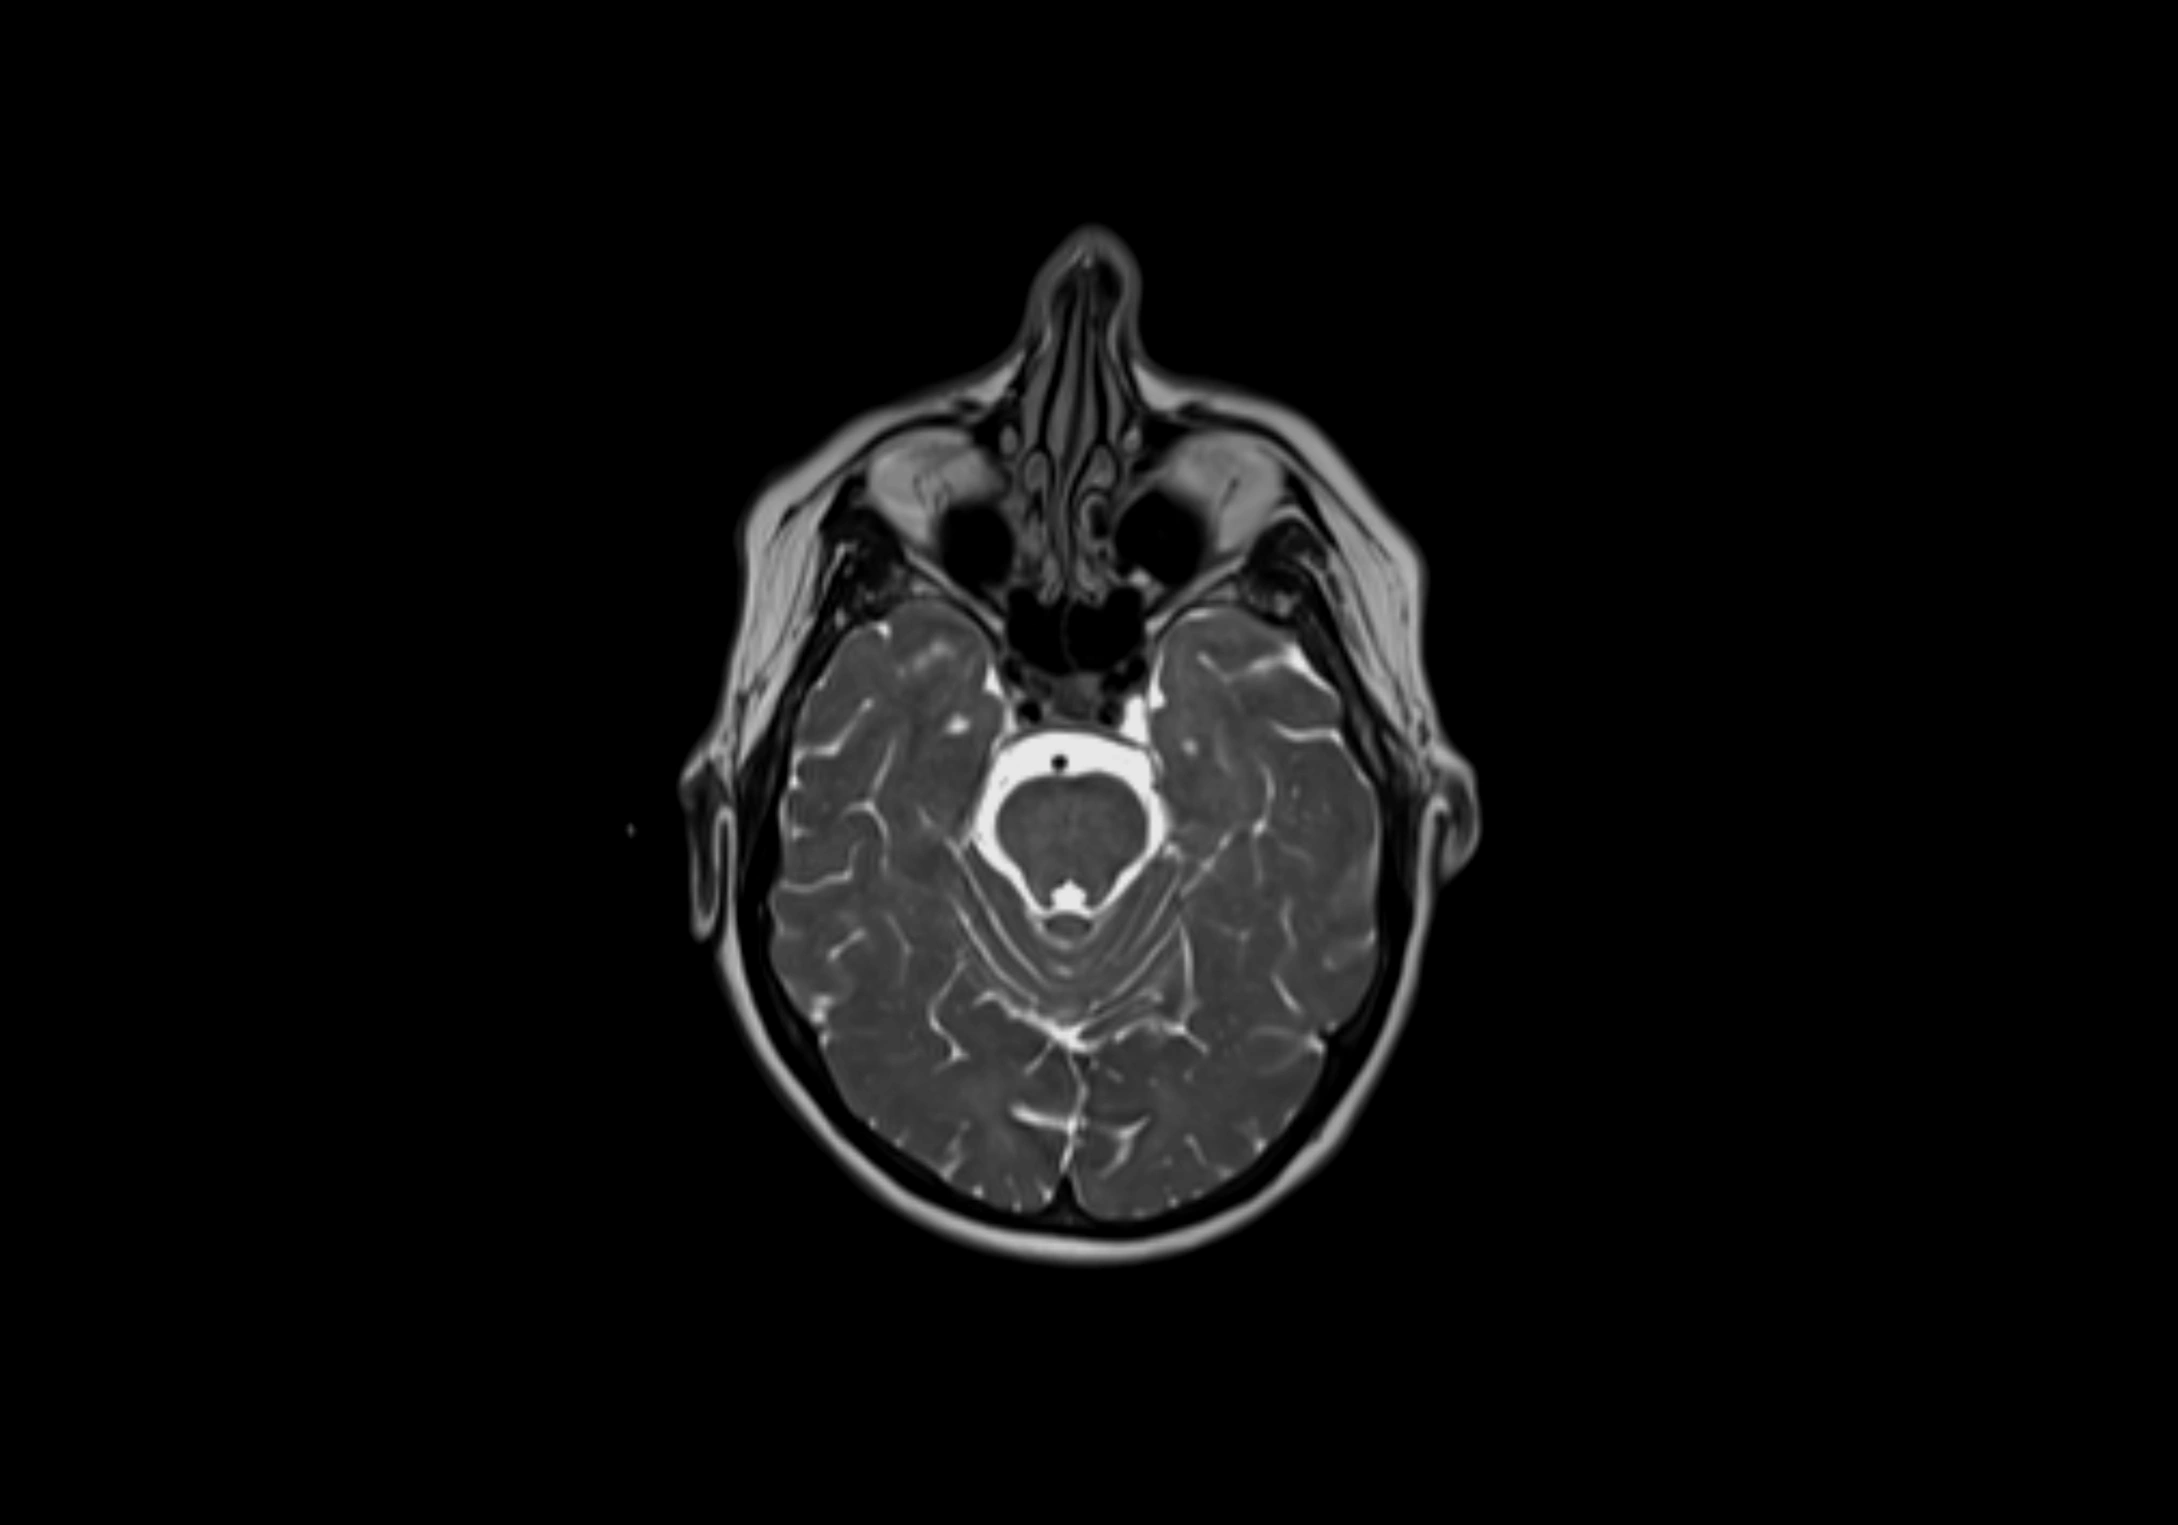

MRI Appearance

T2-weighted images:

• Nodes show intermediate signal, with surrounding fat bright

• Useful for detecting edema, inflammation, or infiltration

• Fatty hilum may appear slightly hyperintense relative to cortex

STIR (Short Tau Inversion Recovery):

• Fat suppression enhances visualization of edematous or pathological nodes

• Normal nodes appear low to intermediate signal, while inflamed or metastatic nodes appear hyperintense

• Useful for detecting subtle lymphadenopathy or early pathology